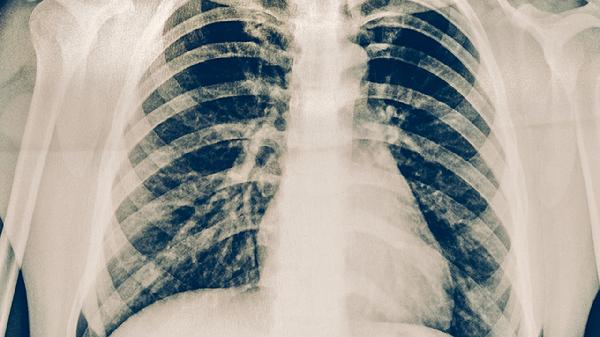

肺尖部因直立位时血流量较少且氧分压较高,为结核分枝杆菌提供了适宜繁殖环境。上叶后段支气管走行陡直且分泌物易滞留,导致局部防御功能下降。下叶背段因重力作用易发生分泌物积聚,同时该区域淋巴回流较慢。病灶多表现为渗出、增生或干酪样坏死,可形成空洞或纤维化。部分患者可能出现咳嗽、低热、盗汗等症状,影像学检查可见斑片状或结节状阴影。

确诊后需规范使用异烟肼片、利福平胶囊、吡嗪酰胺片等抗结核药物,治疗期间应保证充足营养和休息。避免与他人密切接触,咳嗽时掩住口鼻。定期复查胸部影像学及痰菌检查,观察病灶变化。保持居住环境通风干燥,适当进行有氧运动增强免疫力。出现咯血或呼吸困难等症状需立即就医。